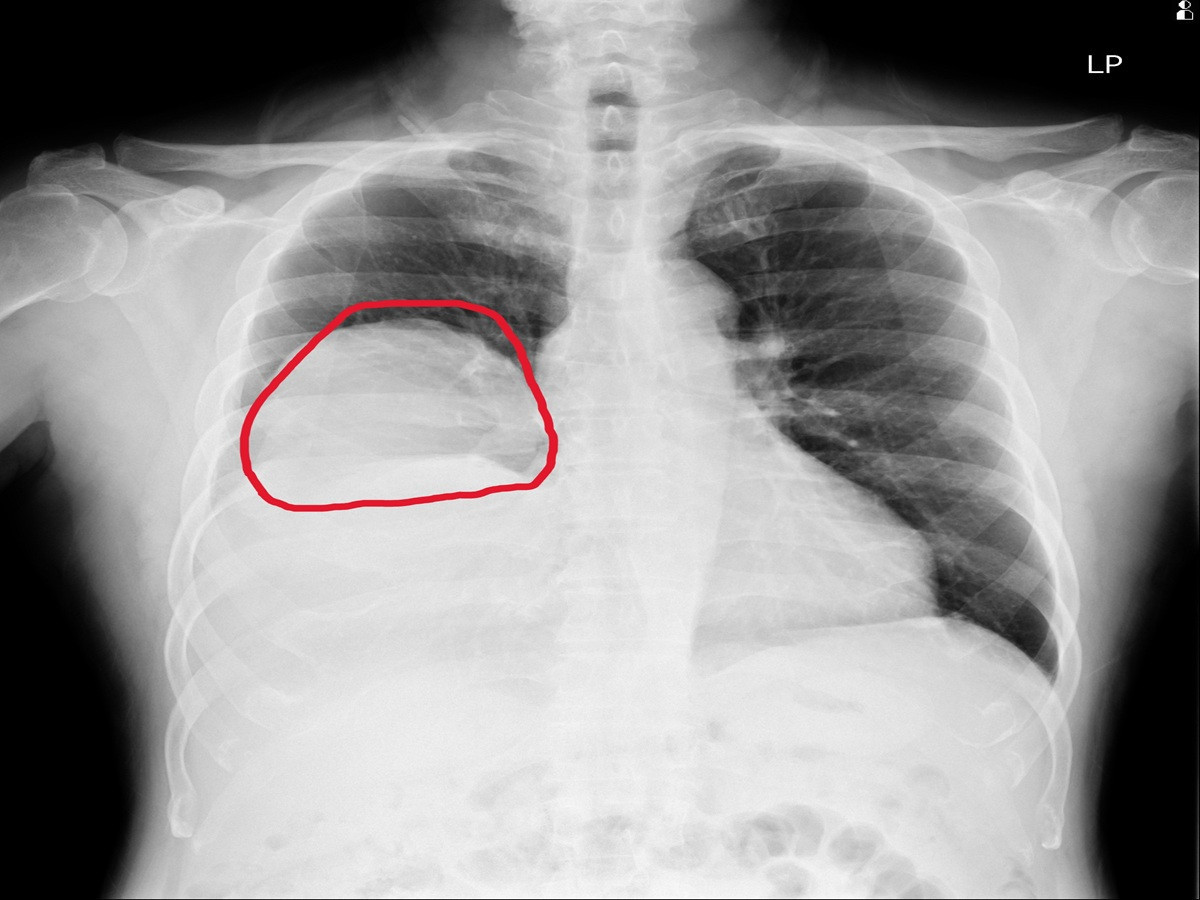

住院期間,患者仍頻繁出現低血糖發作,甚至血糖多次低於30 mg/dL,需持續補充高濃度葡萄糖維持穩定。進一步透過胸部X光與電腦斷層檢查,發現右肺有一顆巨大腫瘤,影像顯示約15×11公分,且壓迫周邊結構,並伴隨肋膜積液與淋巴結腫大情形。

因此會診胸腔內科醫師涂川洲副院長,醫療團隊評估後高度懷疑為「腫瘤相關低血糖」,可能與腫瘤分泌類胰島素生長因子(IGF-2)有關,屬於罕見的「非胰島素瘤性低血糖症(NICTH)」。此類情況多見於大型腫瘤,尤其是間質性或纖維性腫瘤。

術後病理報告確認為罕見的「肺部單發性纖維瘤」,此類腫瘤並不常見,且約有5%的患者會合併低血糖症狀,屬於典型的腫瘤伴隨症候群表現。